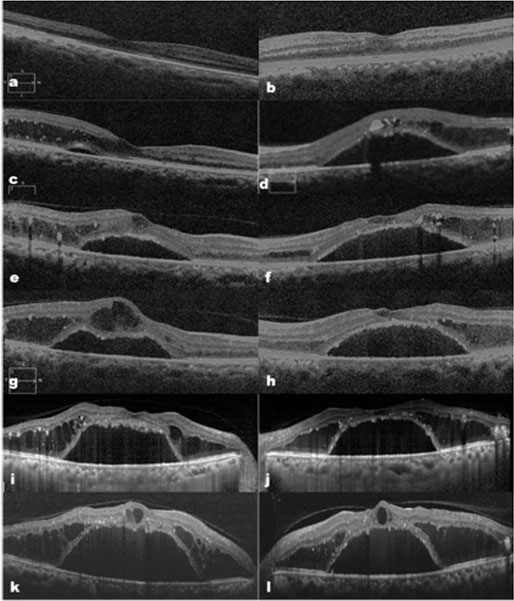

Picture 1: Case-1, showing background diabetic retinopathy with bilateral serous detachment (arrow heads) of the macula (a, b). Corresponding OCT picture showing large foveal detachment with surrounding outer retinal cystoid edema (c, d). (Insets show level of macular scans).

Picture 2: Case-1 with series of OCT scans (c-i) through macula over 12 months showing progressive increase in foveal detachment and outer retinal cystoid separations. (a, b are scans 2 years before the onset of symptoms showing near normal macular configuration)

Picture 3: case-2fundus showing appearance of engorged retinal venules (arrows) in both eyes over background diabetic retinopathy changes (a, b). OCT pictures (c, d) showing asymmetrical foveal detachment with intraretinal cystoid edema which received multiple anti-VEGF injections. (Insets show level of macular scans).

Picture 4: case-3 fundus shows backgrounddiabetic retinopathy with central serous detachment of macula (a, b). Corresponding OCT pictures confirming serous detachment with intraretinal cystic changes (c, d). (Insets show level of macular scans).